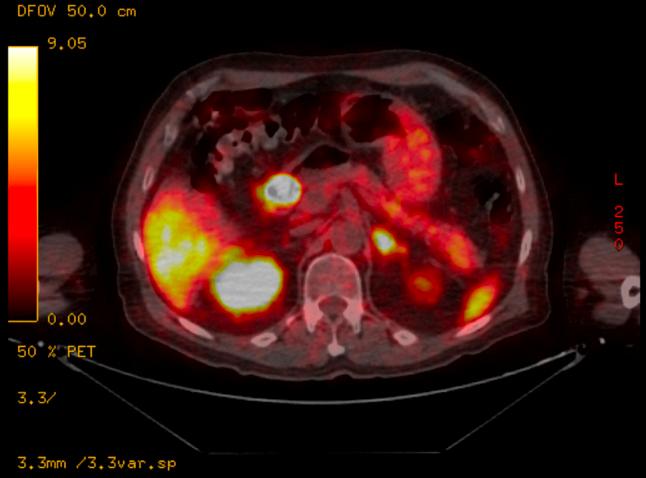

Complete esophageal obstruction (CEO) is a rare phenomenon usually observed after receiving head and neck radiation. Zollinger-Ellison syndrome (ZES) is typically associated with minimal esophageal morbidity because of advancements in antisecretory medications. There are currently no documented reports of CEO in patients with ZES. Although surgeries are available for the treatment of CEO, there is no established method for endoscopic lumen restoration, given its rarity. This case documents potential sequala of modern-day patients with ZES.

完全性食管梗阻(CEO)是一种罕见现象,通常在接受头颈部放疗后出现。由于抗分泌药物的进展,卓艾综合征(ZES)通常与最小的食管发病率相关。目前尚无ZES患者发生CEO的文献报道。尽管有手术可用于治疗CEO,但鉴于其罕见性,尚无成熟的内镜管腔恢复方法。本病例记录了现代ZES患者的潜在后遗症。